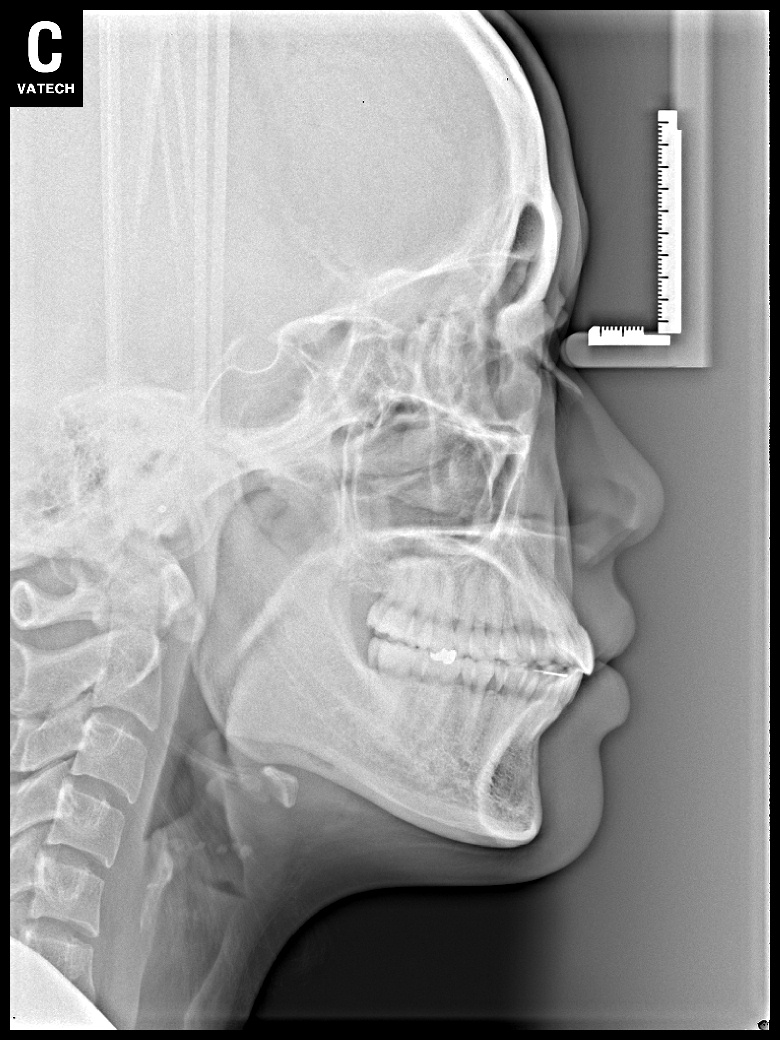

치료 후 사진입니다.